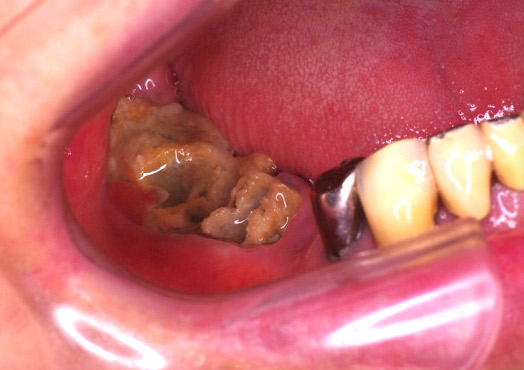

口腔がん

口腔にもがんができます。口腔がんは全てのがんのうち1%と言われていますが、年間2万人以上が罹患する疾患です。

口腔がんはほとんどが扁平上皮癌といわれているものです。その他にも他部位からの転移や、肉腫、悪性リンパ腫など悪性腫瘍が生じます。

口腔がんの治療法には、手術療法、放射線療法、化学療法が標準治療としてあります。切除可能であれば手術療法が基本となりますが、近年は化学療法も抗癌剤のほか、分子標的治療薬なども出てきております。

当院では、手術療法、放射線療法、化学療法対応可能ですが、がんの大きさや種類によっては、当院でも対応困難な場合がありますので、その場合は高次医療機関に紹介させていただくことがあります。